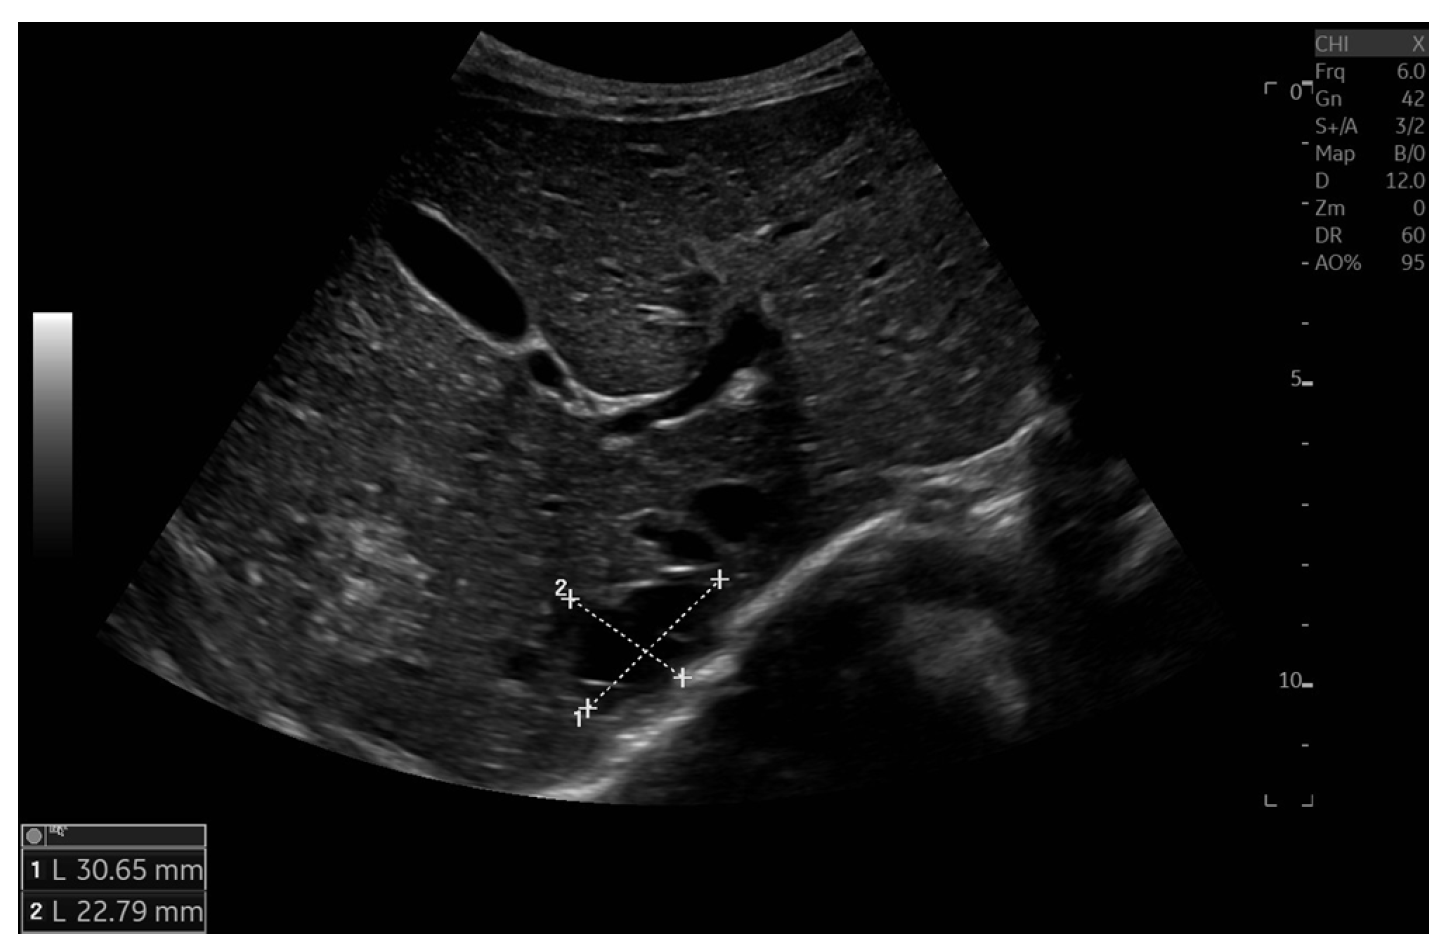

Currently, the boy is 5 years old. The US is similar to the previous one: elevated kidneys length (right: 130 mm (z-score 6.19); left: 133 mm (z-score 6.50)), with increased echogenicity, blurred corticomedullary differentiation, and multiple cysts with a maximum diameter up to 13–15 mm. The liver has a normal size, with numerous cysts up to 16 mm in diameter, with the largest cluster of cysts measuring 43 × 23 × 31 mm (Figure 3 and Figure 4). Laboratory tests show increased creatinine 0.79 mg/dL, urea 69,6 mg/dL, cystatin C 1.71 mg/L, uric acid 6.9 mg/dL, urine albumin to creatine ratio (ACR) 118.6 mg/g, and decreased GFR 55 mL/min/1.73 m2—stage III CKD. Other tests, including electrolytes, liver function, and urinalysis, were normal. The boy demands antihypertensive multi-drug therapy: angiotensin-converting enzyme inhibitors (ACEIs), calcium channel blockers, and beta-blockers.

Figure 3. Ultrasonography of kidneys at the age of five years.